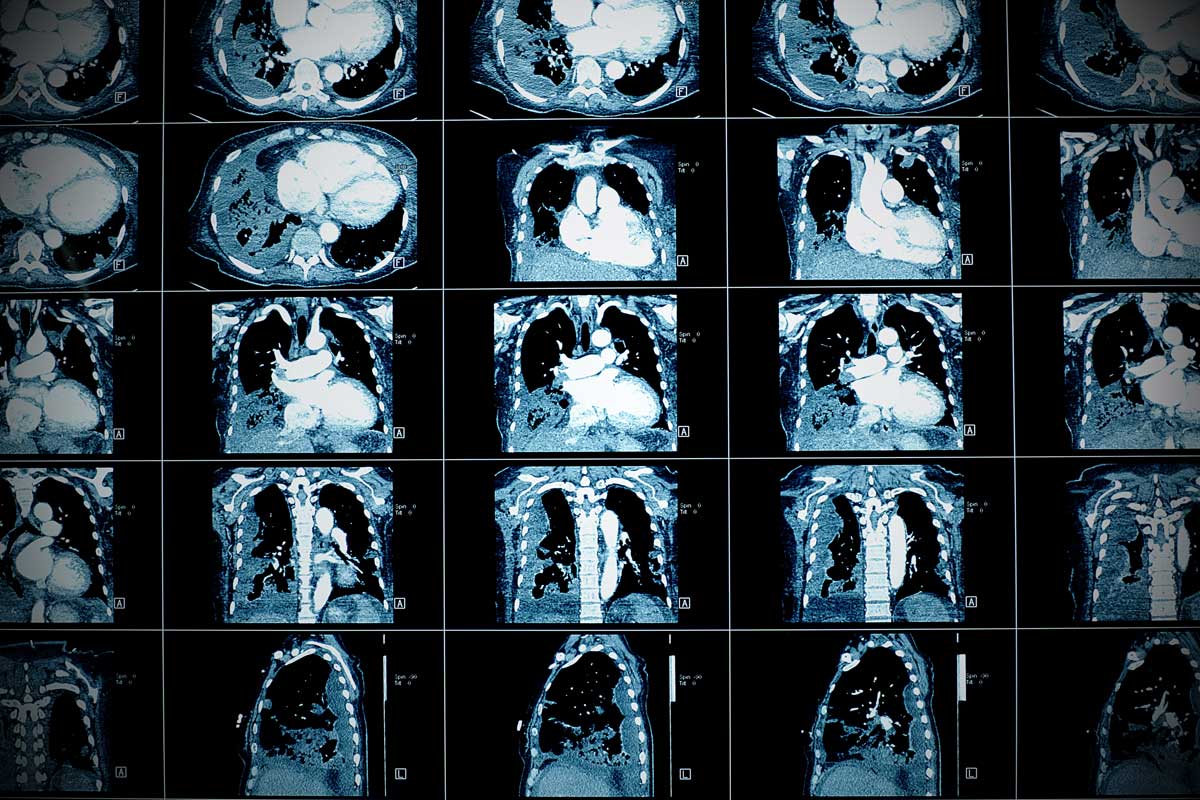

در اکو قلب چه چیزی مشخص میشود ؟ اسکن قلب چیست؟ اسکن قلب برای تشخیص دقیق تر بیماری توسط متخصص قلب و عروق توصیه می شود. هزینه آزاد این روش تشخیصی در برخی مراکز درمانی کمی بالا خواهد بود. البته بیمارستان های دولتی هزینه مقرون به صرفه ای بابت اسکن قلب دریافت خواهند کرد که از لحاظ کیفیت ممکن است چندان قابل اعتماد نباشند.

اسکن قلب از خدمات تحت پوشش بیمه دانا در مراکز دولتی و برخی مراکز خصوصی است. بهترین مرکز خصوصی را برای اسکن قلب کلینیک ویستان ارائه می دهد. این مرکز با در اختیار داشتن بهترین متخصص قلب و عروق در مرزداران و غرب تهران و مراکز خصوصی اسکن قلب بیمه دانا، خیالتان از بابت نتیجه درست آزمایش را راحت می کند.